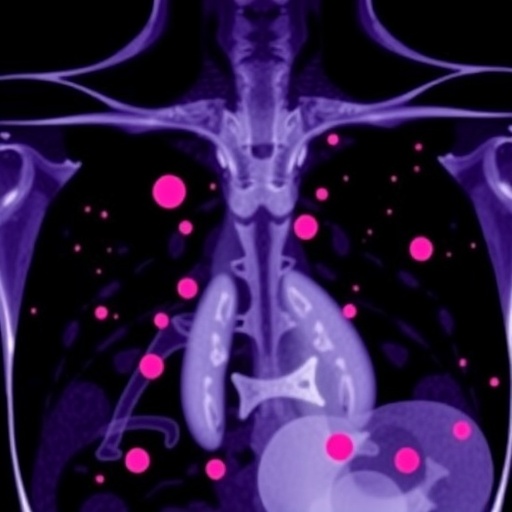

In the evolving landscape of cancer treatment, a pivotal study uncovers promising results involving the combination of Sitravatinib and Tislelizumab for patients grappling with locally recurrent or metastatic triple-negative breast cancer (TNBC). Conducted as part of the SPARK Trial, this multi-cohort, single-arm phase II clinical trial has gained attention for its innovative approach. The study, led by researchers including Liu, Sui, and Xu, delves into the efficacy of this therapeutic combination, marking a potential breakthrough in the treatment of one of the most aggressive forms of breast cancer.

Triple-negative breast cancer is known for its lack of three key receptors: estrogen, progesterone, and the HER2 protein. This deficiency renders traditional treatment options like hormone therapy and targeted HER2 therapies ineffective, leaving many patients with limited choices. The SPARK Trial aims to address this urgent need for new treatment strategies by exploring how Sitravatinib, an oral drug inhibiting multiple receptor tyrosine kinases, can enhance the anti-tumor effects of Tislelizumab, a potent PD-1 inhibitor.

In the realm of metastatic breast cancer, where the disease has spread beyond the primary tumor site, the stakes are particularly high. The burden of metastasis often signifies a shift to advanced disease, with a corresponding decline in treatment options. Thus, any new avenues to treat these patients are of paramount importance. The SPARK Trial seeks to redefine the treatment landscape, offering hope that a combination of Sitravatinib and Tislelizumab may translate into longer survival times and improved quality of life for this vulnerable population.